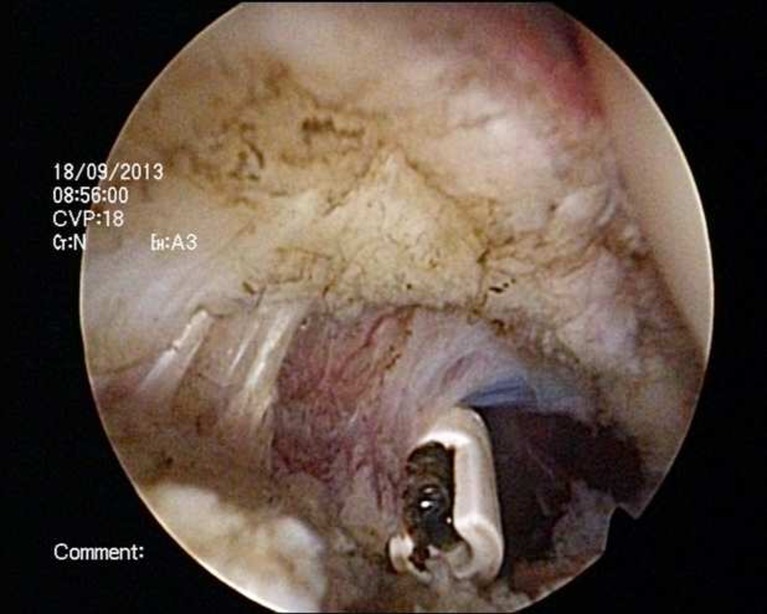

Fig. 1.

Anterior capsular release in a patient with post-traumatic stiff shoulder

Arthroscopic capsular release

The surgery was performed in a routine way as previously described [6]. All patients were operated on in the beach-chair position. Passive range of motion was documented under general anaesthesia and interscalene block before surgery. Standard posterior portal was used. After insertion of the arthroscope, anterior portal was established by using an ordinary needle which was placed in a rotator interval from outside-in. Release of the rotator interval was first performed, and then contracted, then the anterior capsule was released followed by the posterior capsule by a radiofrequency device looking from anterior portal (Figs. 1 and 2). A small part of the capsule in the axillar region was not released. After the arthroscopic release, manipulation of the shoulder was performed. In all cases minimal force was required to restore full range of motion. Subacromial bursectomy was performed only in postraumatic cases to exclude some damage of subacromial structures such as partial bursal rotator cuff tear or damage of the anterior-inferior edge of the acromion.